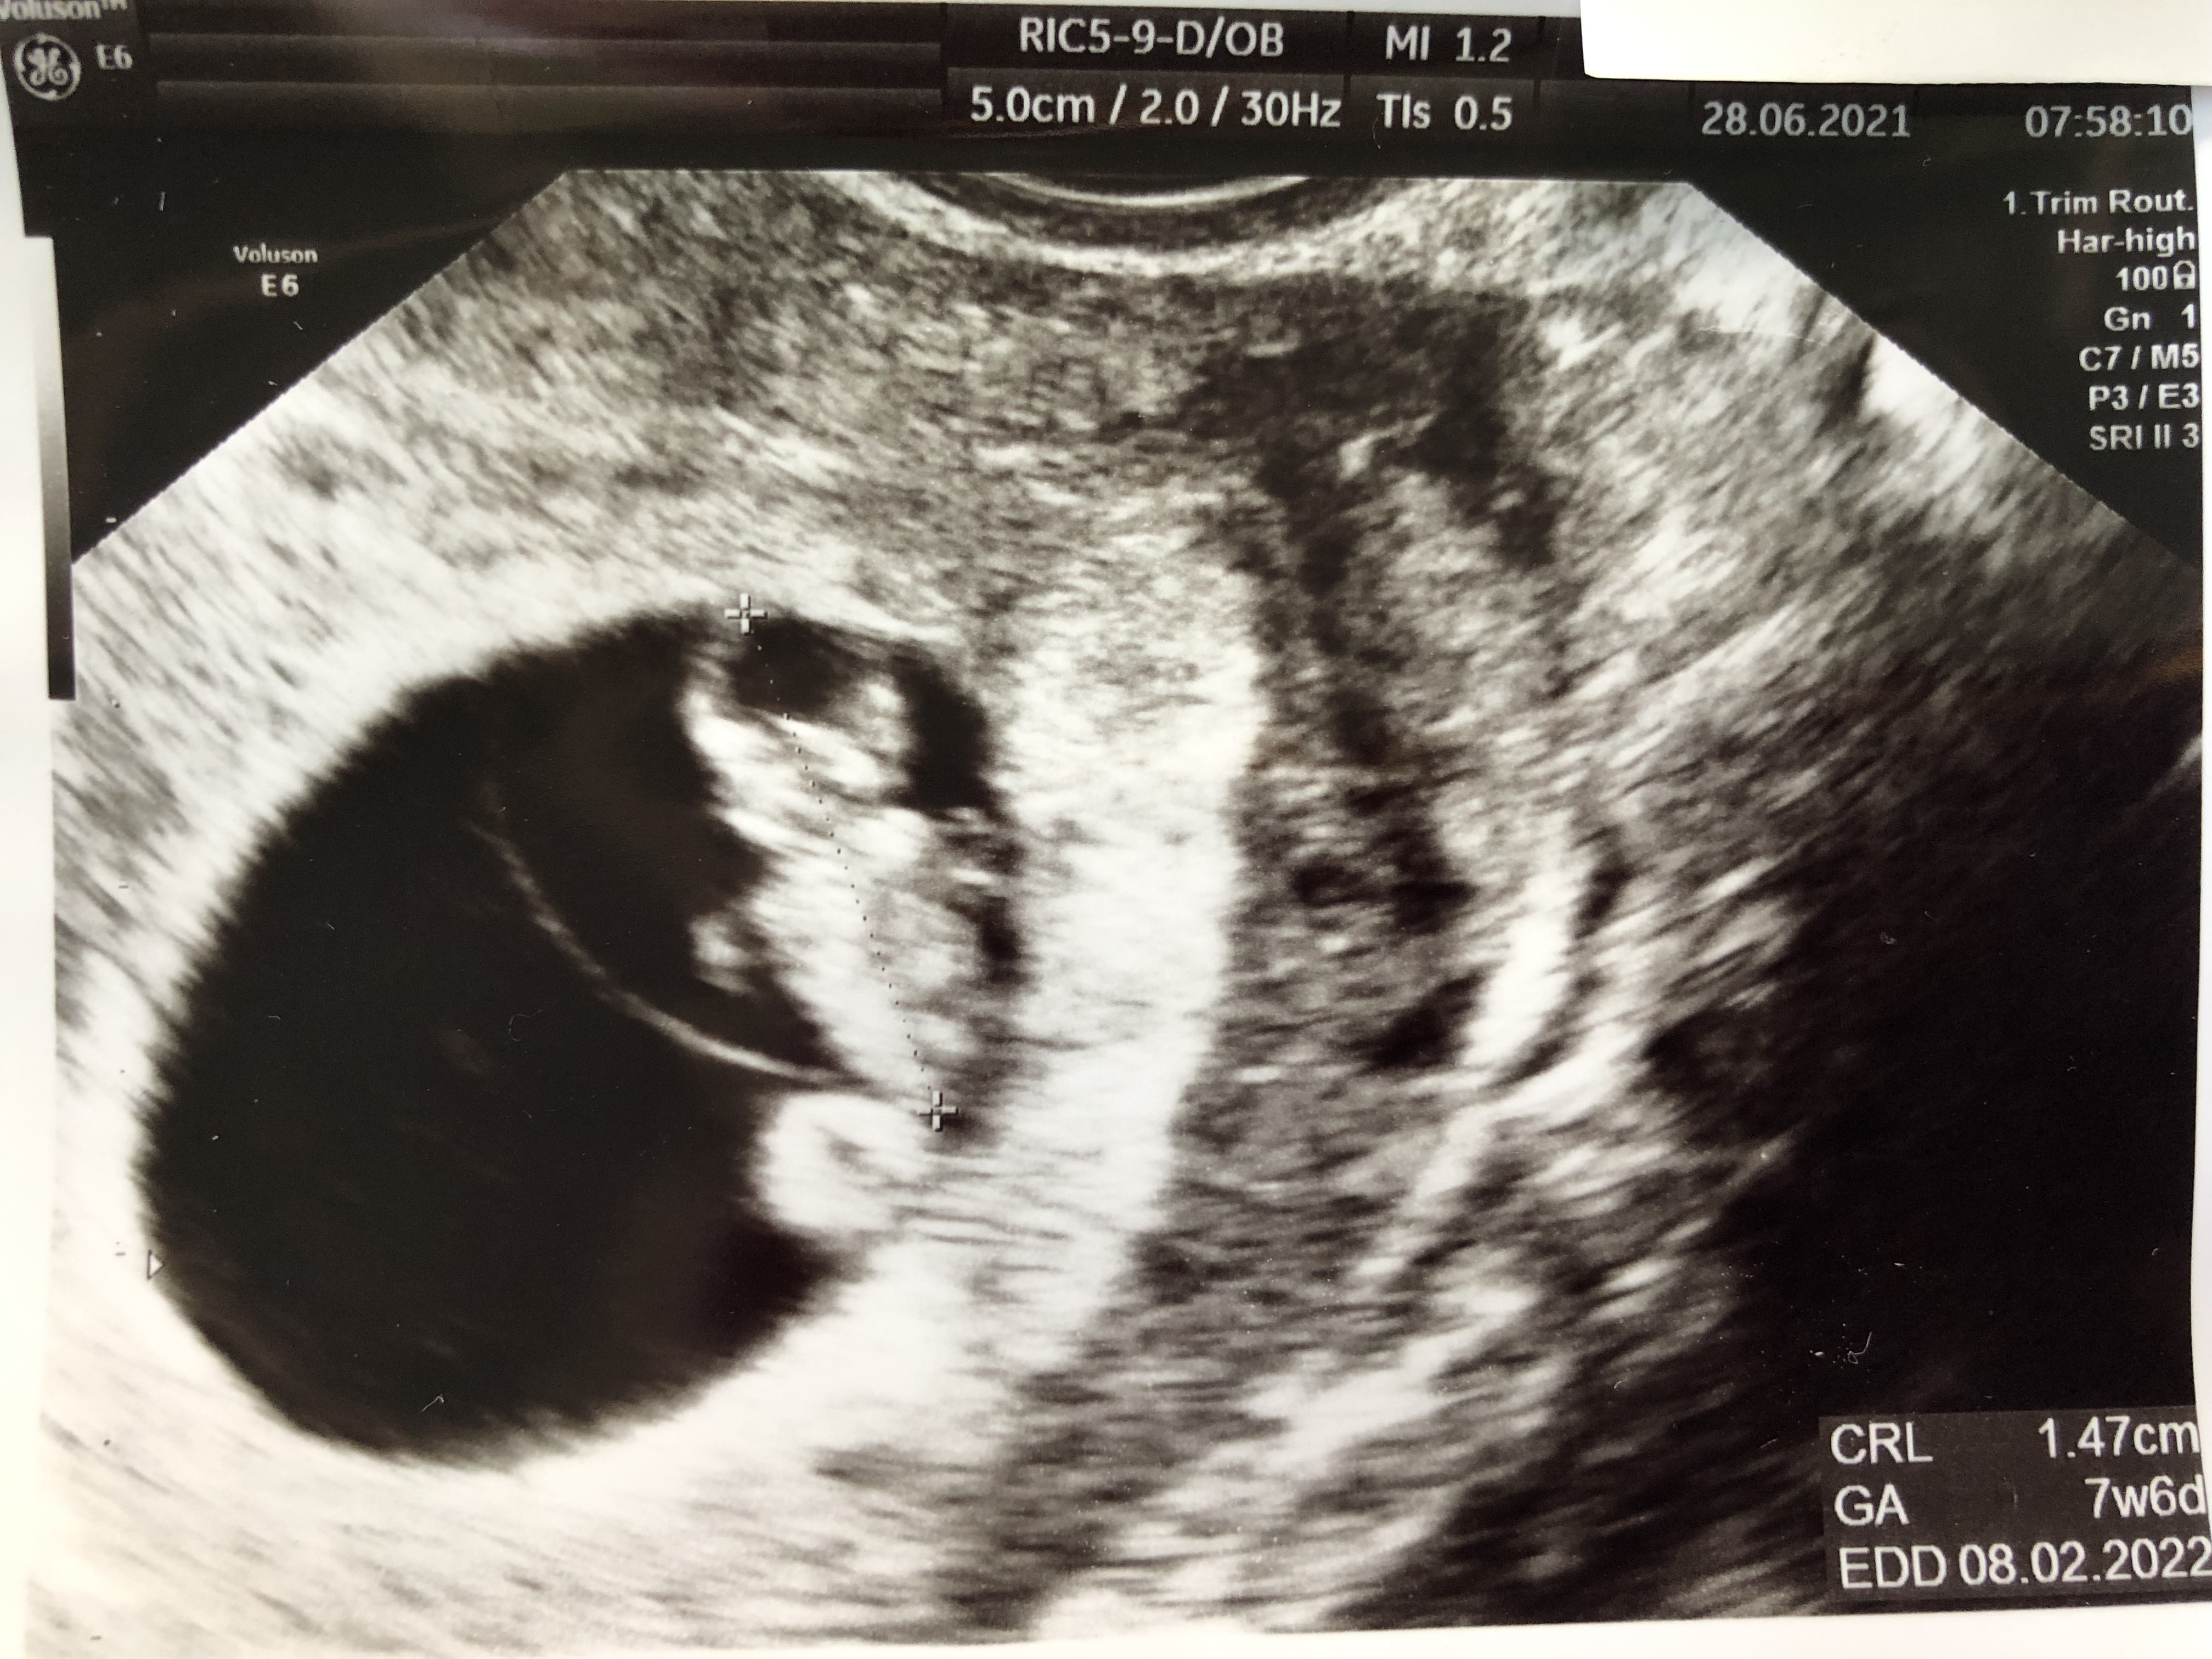

Lubię oglądać swoje (prawie codziennie 😁) i Wasze zdj. Usg. Bardzo ładne już dzieciaczki widać 😊 Ja na bieżąco wstawiałam, 4tyg temu kropeczkę i 2 tyg. temu fasolkę (lub oby dwa jednocześnie, nie pamiętam. Ale w piątek byłam na nieplanowanej wizycie u innego gin. i miał tak bardzo stare usg, i prawie nic nie było widać. No i brak łazienki w gabinecie, rozbierałam się przy nim 🤦‍♀️ Wstawię Wam dla porównania z 2 tyg temu i piątek. Teraz się nie dziwię, że niektórzy szybciej zobaczyli zarodek a inni czekali. I że na niektórych zdj widać już małego człowieczka, a u innych w podobnym tyg nie wiadomo co (tutaj mówię o swoim zdj i ogólnie obrazie usg) Już się nie mogę doczekać wizyty w pon żeby zobaczyć dokładniej rączki i nóżki no i ogólnie całokształt. Jestem w szoku, że prywatnie można spotkać tak stare sprzęty. Na NFZ wcale by mnie to nie zaskoczyło, ale w jednym i w drugim gabinecie płaciłam 200zł…

• 3B7459AC-4D37-4330-ABEB-348B1EE87448.jpeg

3B7459AC-4D37-4330-ABEB-348B1EE87448.jpeg

2 MB · Wyświetleń: 85